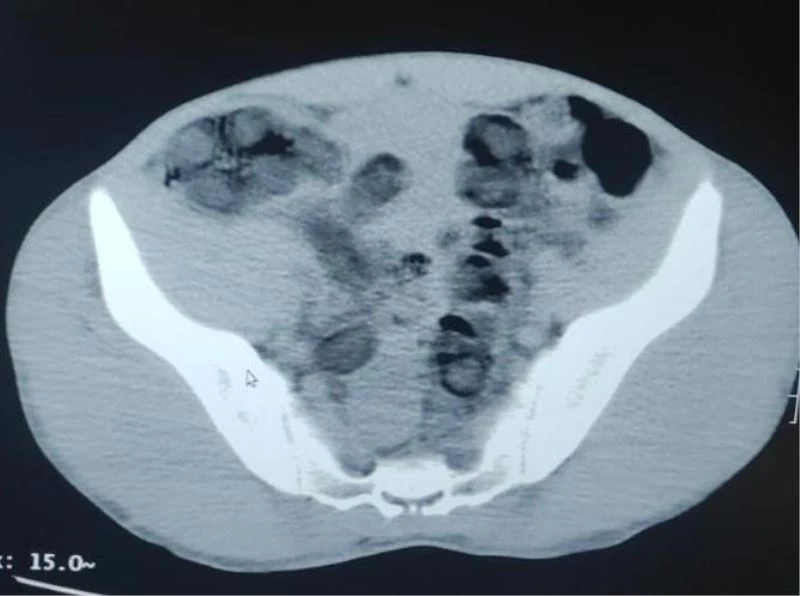

Bitlis Valiliğinden yapılan açıklamada, "Bitlis İl Jandarma Komutanlığı unsurlarınca yapılan istihbari çalışmalar neticesinde, Güroymak ilçesi Günkırı mevkiinde icra edilen yol kontrol faaliyetinde, Van-İstanbul seferini yapan bir yolcu otobüsünde iki şüphelinin vücutlarında uyuşturucu madde taşıdıkları bilgisi alınmıştır. Şüphelilerin çekilen tomografi ve röntgen görüntülerinde mide ve bağırsaklarında yabancı cisim olduğu tespit edilmiştir. Yapılan operasyonla her iki şüphelinin midesinden toplam 176 adet kapsül içerisinde 1 kilo 96 gram eroin maddesi ele geçirilmiş, şüpheli 2 şahıs gözaltına alınmıştır. Gözaltına alınan 2 şüpheli adli işlemlerinin tamamlanmasına müteakip 22/23 Şubat günlerinde adli makamlara sevk edilmelerine müteakip tutuklanarak Bitlis kapalı cezaevine teslim edilmiştir. Yarınlarımızın teminatı olan çocuklarımızı ve gençlerimizi uyuşturucudan korumak maksadıyla, uyuşturucu madde türevlerinin ticaretini yapan veya sosyal medya aracılığı ile alenen özendiren şahıslarla, yılmadan ve yorulmadan etkin mücadeleye bölge halkının da desteği ile kararlılıkla devam edilmektedir" denildi.